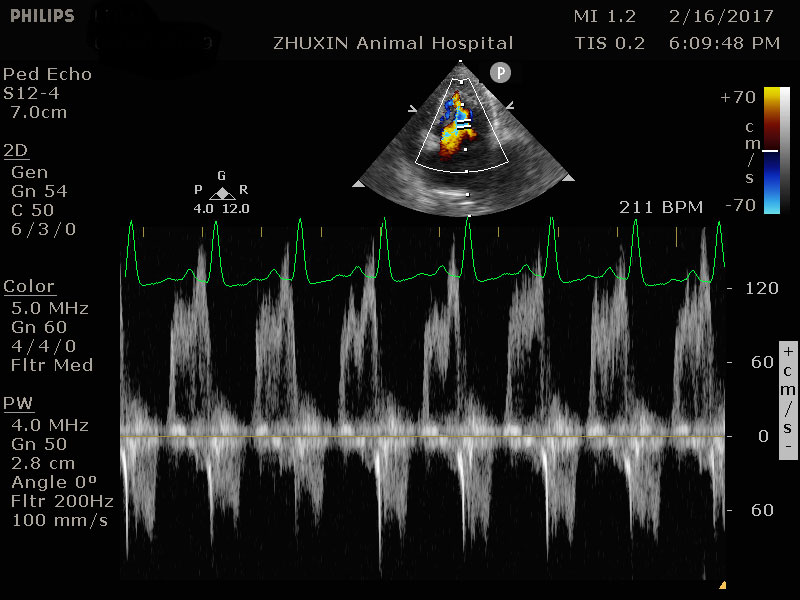

擴張性心肌病的超音波影像

心臟快速掃描結果

嚴重的左心房擴張

左心室壁明顯肥厚